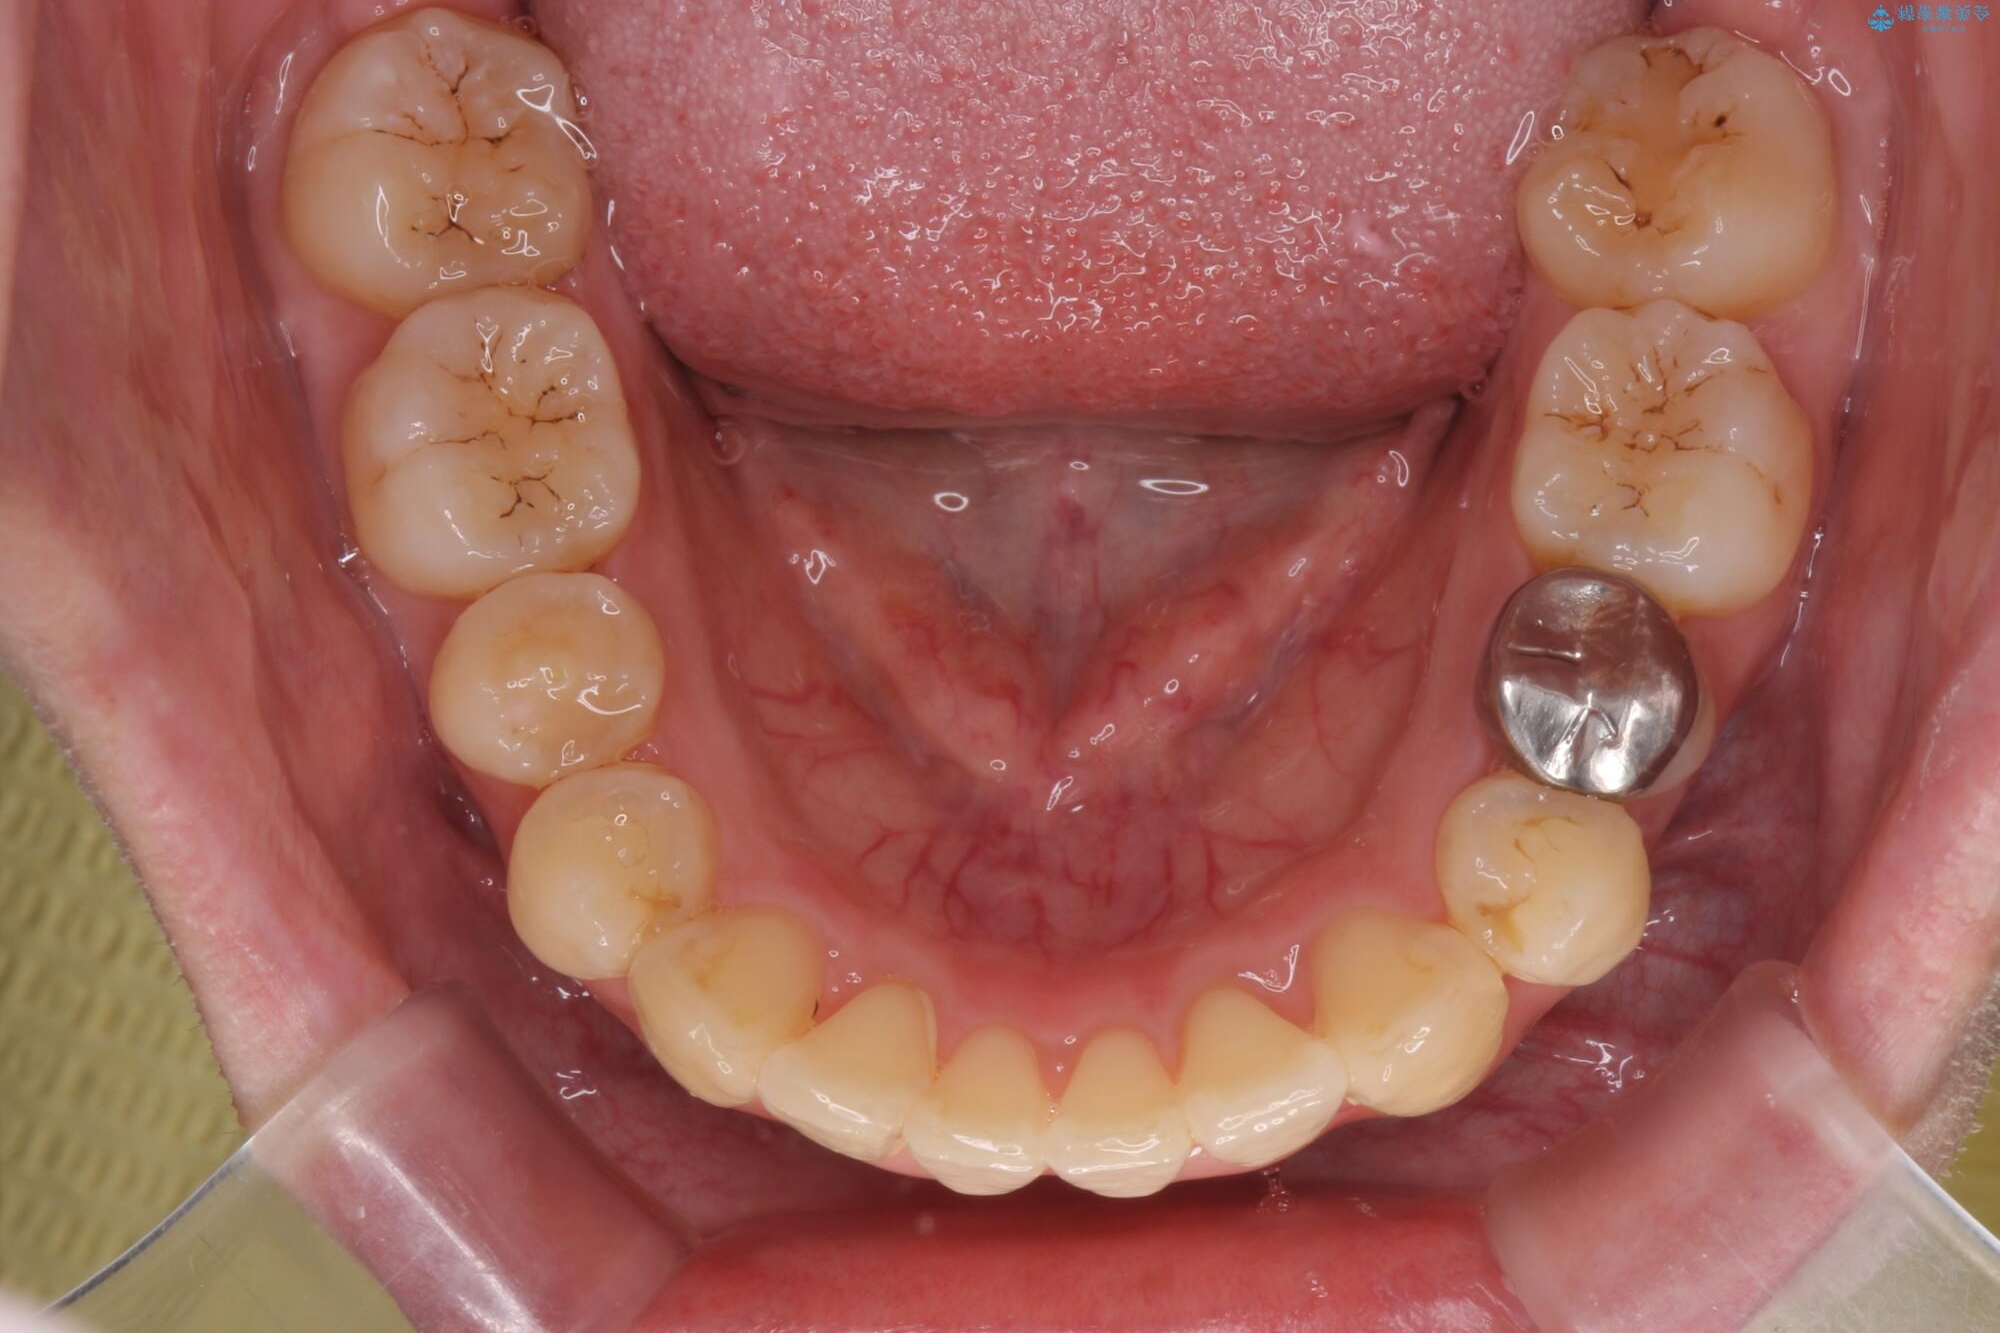

治療前

気になる犬歯のガタつきをマウスピース矯正で改善 治療前画像 気になる犬歯のガタつきをマウスピース矯正で改善 治療前画像 気になる犬歯のガタつきをマウスピース矯正で改善 治療前画像 気になる犬歯のガタつきをマウスピース矯正で改善 治療前画像